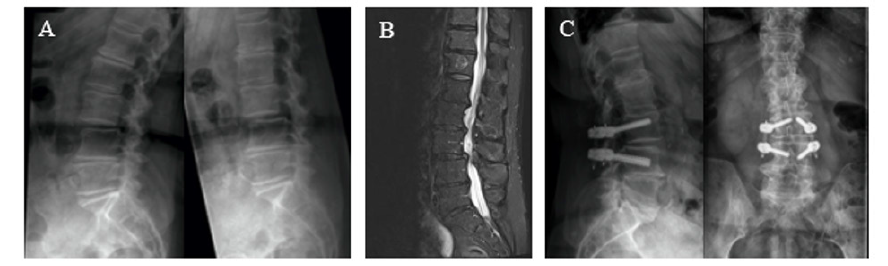

Figure 2: Case example.

Woman, 81 years, preoperative refractory back (VAS 6/10) and leg pain (VAS 6/10), Surgical procedure: Decompression L2/L3, L3/L4 and dynamic stabilization L3/L4.

Follow-up: 16 months. Postoperative stable radiological results and pain reduction for back (VAS 4/10) and leg (VAS 1/10) pain.

A: Preoperative functional radiography showing segmental instability L3/L4 (3 mm, Antherolisthesis Meyerding grade I)

B: Preoperative MRI showing spinal stenosis L2/L3 and L3/L4

C: Postoperative radiography.